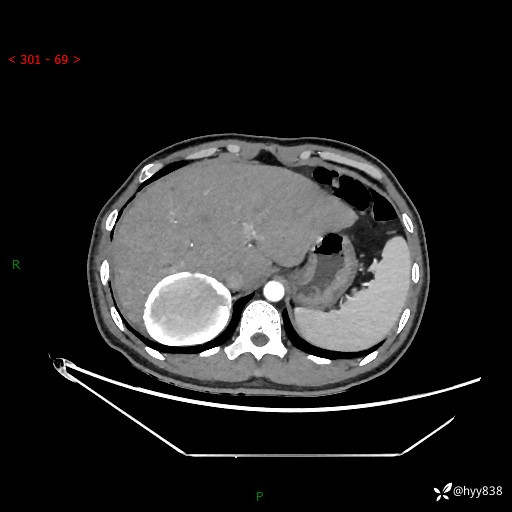

性别:男

年龄:50岁

简要病史:夜尿增多半月,发现肾功能异常1天,超声发现腹膜后占位

腹部CT平扫+增强

增强